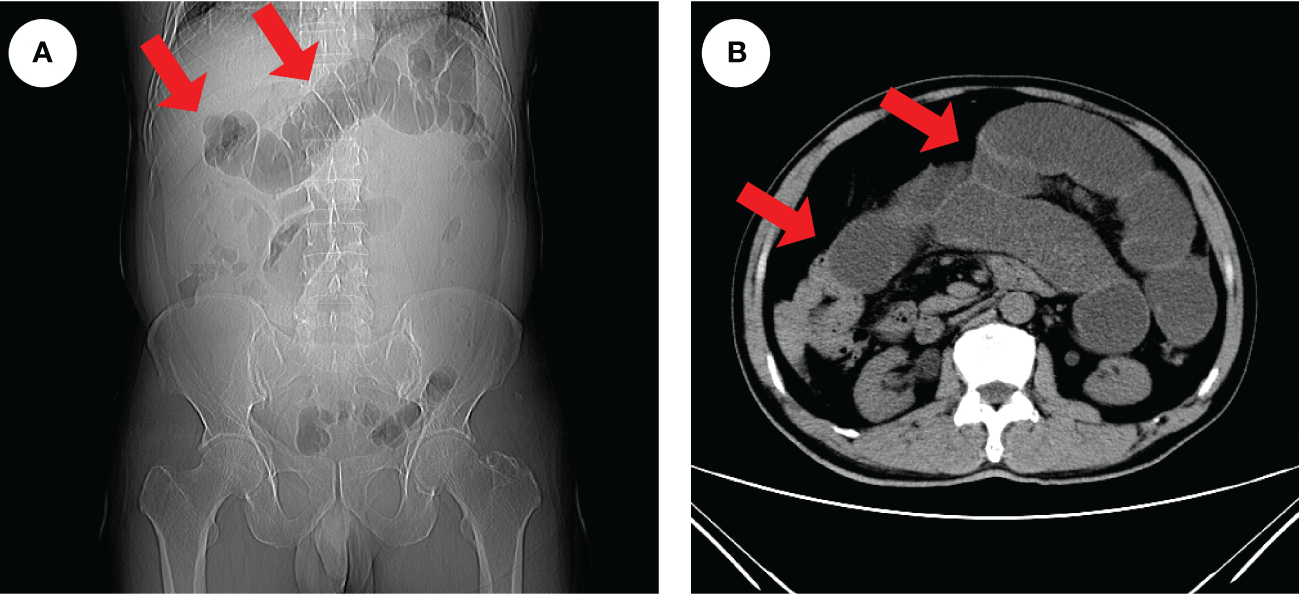

Figure 1

Radiologic findings of intestinal obstruction. An abdominal CT examination in an emergency was performed on the patient and revealed extensive dilatation of the transverse colon (red arrows), indicating proximal intestinal obstruction (A, B).